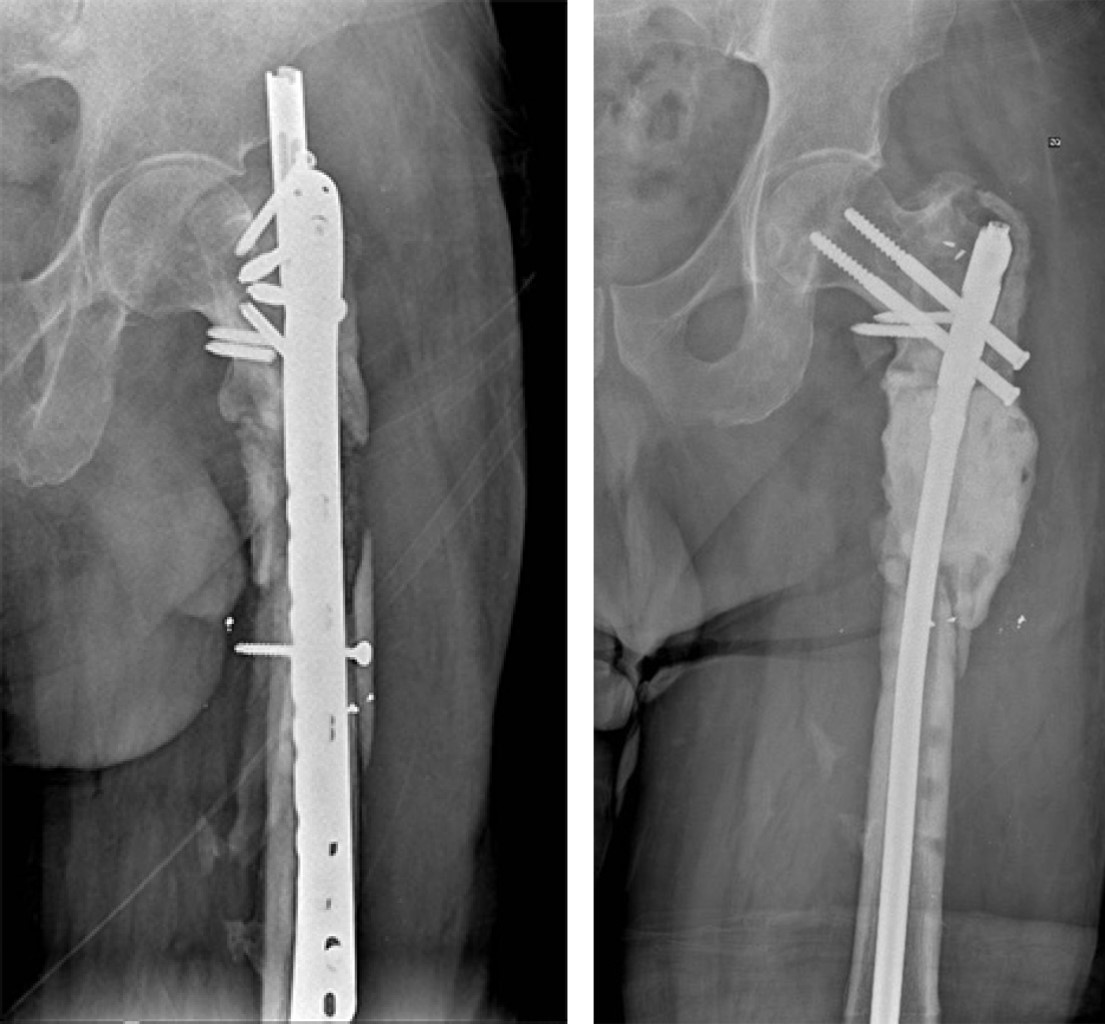

Radiográficamente, se observaba una pérdida de continuidad de la diáfisis proximal del fémur izquierdo, a partir de la zona subtrocantérica, seis centímetros distales con datos de fractura multifragmentada en seudoartrosis tipo III de Karger, al igual que fractura del trocánter mayor no consolidada; fijadas con un clavo centromedular con tornillos proximales de fijación, suplementado con placa lateral fijando el fragmento trocantérico (Figura 1).

En este caso se realizó la técnica de Masquelet en dos etapas, en las cuales se cumplieron los pasos secuenciales procurando obtener un microambiente biológico favorable, esto es: en un primer tiempo quirúrgico se realizó el retiro de clavo centromedular, placa y tornillos de los tratamientos previos, se realizó desbridación extensa de tejido avascular, toma de muestras para cultivo, estabilización y colocación del espaciador con antibiótico (gentamicina) y colocación de clavo centromedular bloqueado (Figura 2).

Figura 1

Figura 2